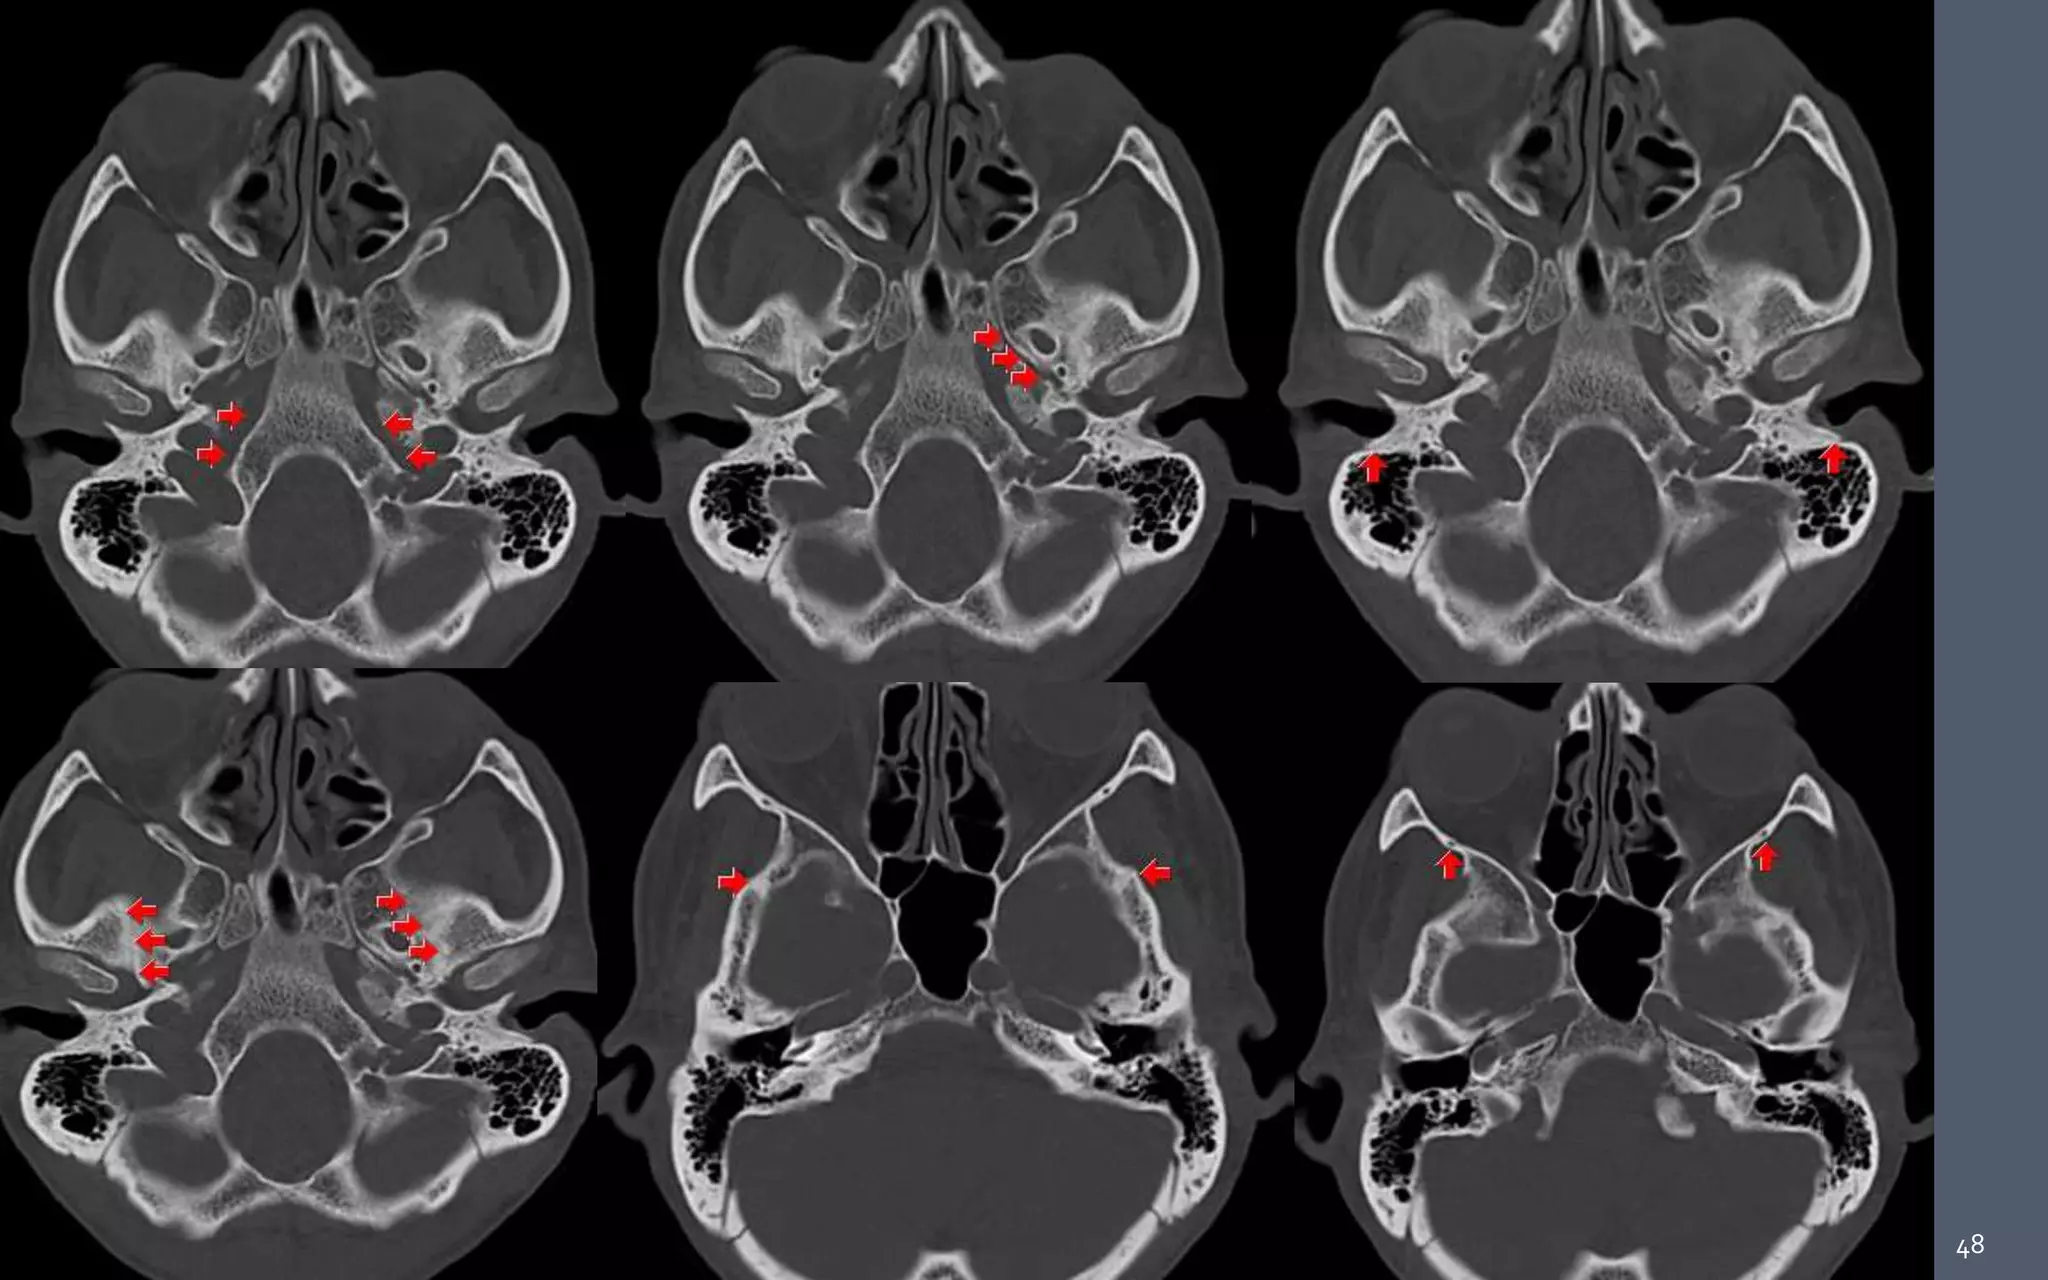

48

 Parapharyngeal , masticator, carotid, and retropharyngeal spaces are

seen in close contact with the skull base along their cephalad aspect .

• #20 The medial red lines pass in the medial aspect of the petroclival synchondrosis (long white arrows). The lateral red lines pass immediately lateral to the foramen ovale. (short white arrow).

• #49 1. Petro-occipital fissure. 2. Petrosphenoid suture. 3. Tympanomastoid suture. 4. Sphenosquomaous suture. 5. Sphenozygomatic suture.